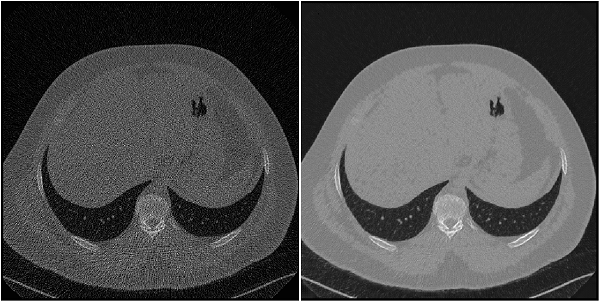

Low Dose CT Grand Challenge

| The Low Dose CT Grand Challenge includes pairs of regular-dose CT images and simulated low-dose CT images for 99 head scans (labeled N for neuro), 100 chest scans (labeled C for chest), and 100 abdomen scans (labeled L for liver) [12] [13]. The full data set is about 1.2 TB. Create a directory to store the chest files from the Low Dose CT Grand Challenge data set.

dataDir = fullfile(tempdir,"LDCT","LDCT-and-Projection-data"); if ~exist(dataDir,"dir") mkdir(dataDir); end To download the data, go to The Cancer Imaging Archive website. Download the chest

files from the "Images (DICOM, 952 GB)" data set using the NBIA Data Retriever. Specify the

For an example showing how to process this data for deep learning, see Unsupervised Medical Image Denoising Using CycleGAN (Image Processing Toolbox). | Image-to-image regression |